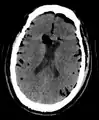

| Pneumocephalus and comminuted fracture of the frontal sinus |